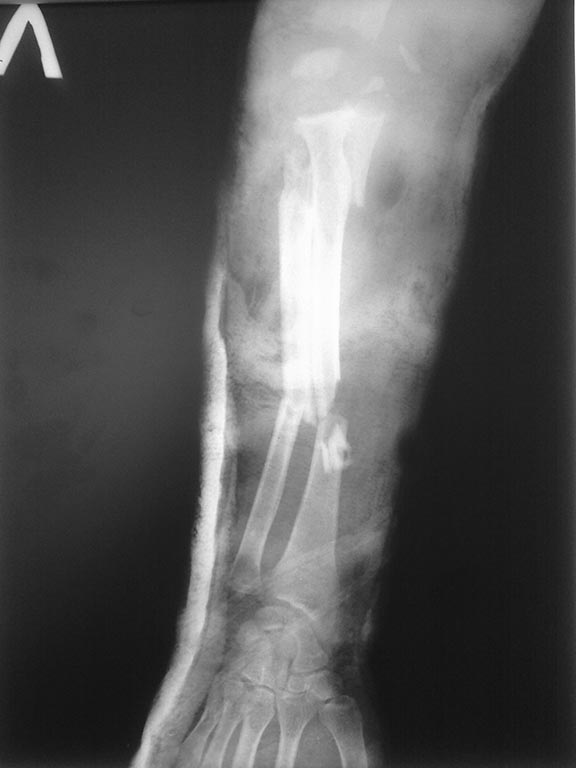

Вот еще снимок.

Какой всё-таки механизм травмы и что из себя представляют местные мягкие ткани? Учитывая последний снимок : сделать остеосинтез диафизов костей предплечья. АВФ на локтевой сустав с удержанием плечевой кости и костей предплечья в виде "виртуального локтевого сустава". В дальнейшем - скорее всего эндорпротезирование. Всё же.. Как с мягкими тканями? Насколько повреждены? Что с нервами?